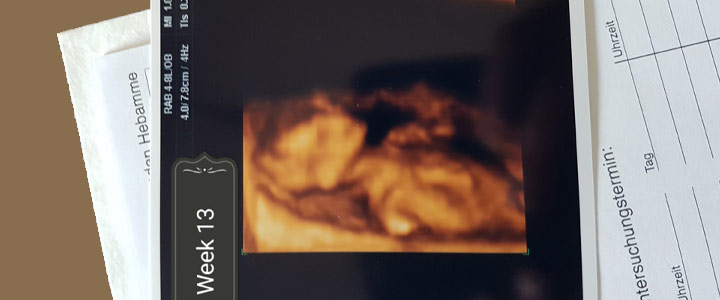

De combinatietest 3d echo blog 13 weken

De combinatie test Vandaag weer bij de frauenartz geweest voor de combinatie test. De nekplooi meting en bloed onderzoek. De arts heeft van alles gemeten. Armpjes, beentjes, het hoofdje en de nekplooi heeft ze gemeten. Alles zag ...